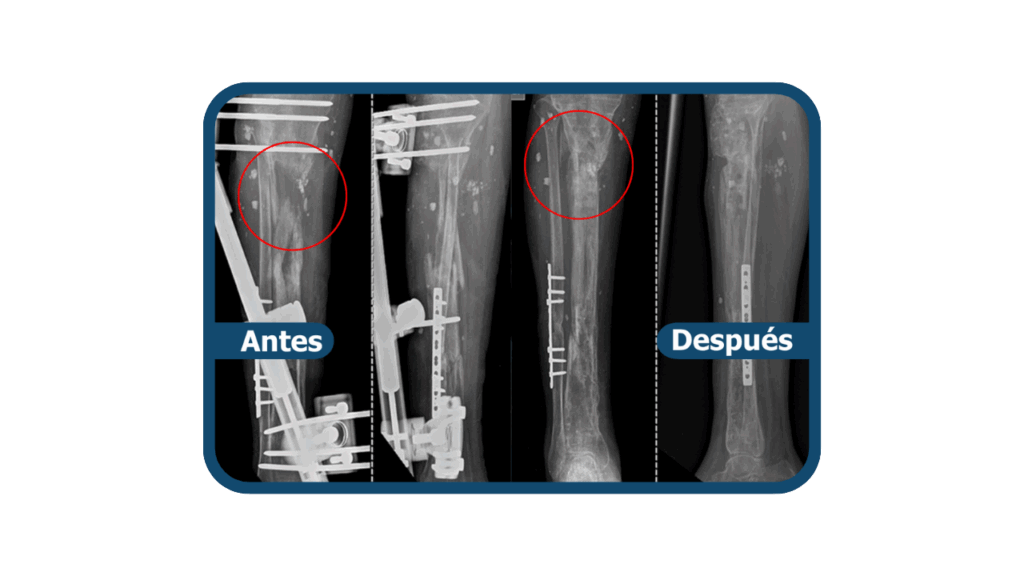

La pseudoartrosis es una infección ósea en la que un hueso fracturado no logra consolidar correctamente, provocando dolor y falta de estabilidad. Es también una infección muy común en Clínica Arthrosalud, y es tratada adecuadamente por nuestros traumatólogos especialistas. Lo fundamental para el paciente que padece esta condición, es la prevención para evitar complicaciones en su articulación a futuro.